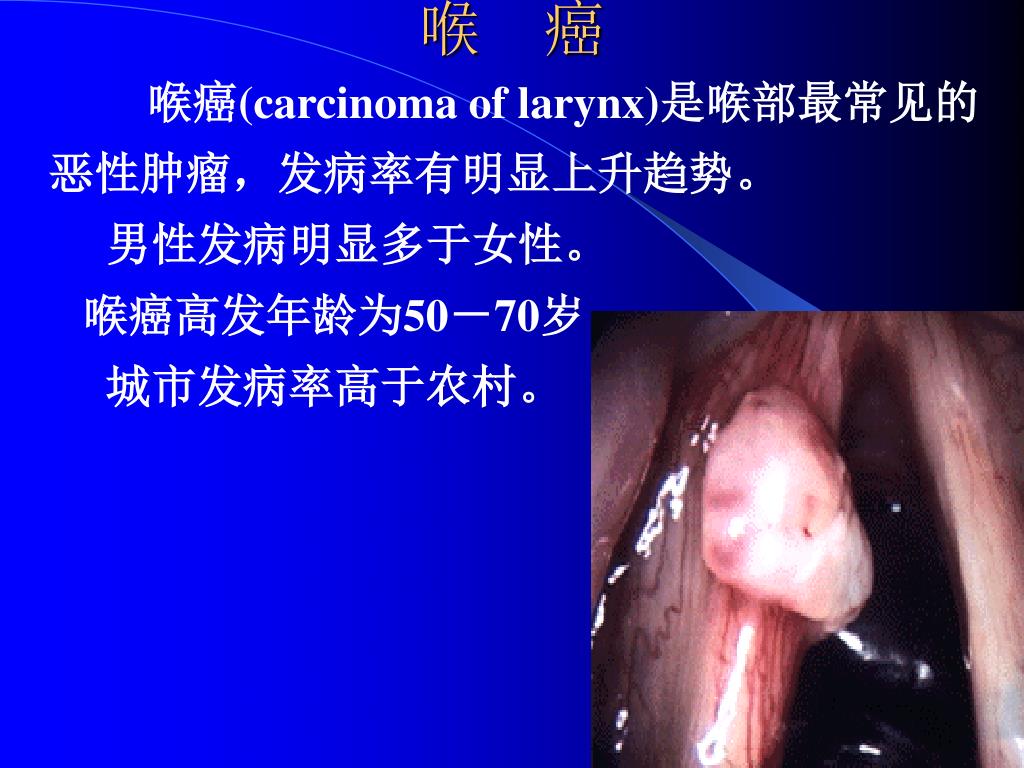

Ppt 喉癌powerpoint Presentation Free Download Id 3651007

早期喉癌经治5年生存率可达90 几大诱因易致喉癌复发 喉癌 瑞得生健康网